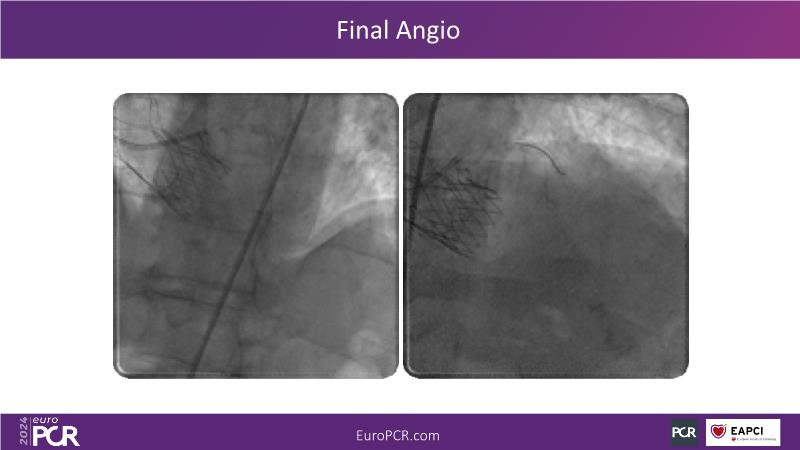

Watch this session on PCI in diabetic patients to learn about a groundbreaking technology addressing the complexities of this critical subgroup. Discover the next-generation DES and DCB stent platform and the innovative Envisolution technology behind it. Understand how it works, its advantages in managing complex cases, and what sets it apart from other technologies. Gain insights into the future of polymer-free DES + DCB stent technology and its potential impact on patient care.